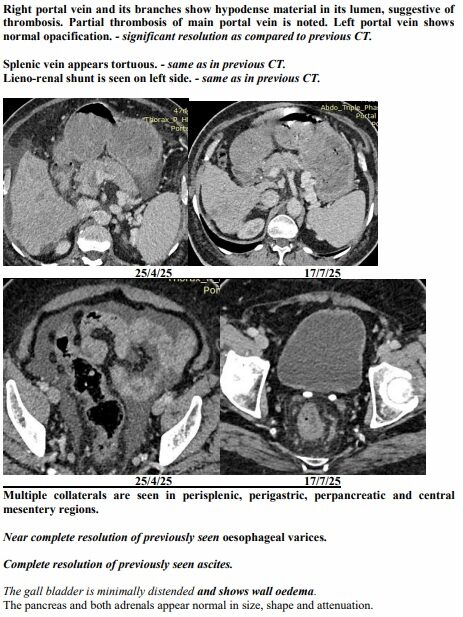

Yet just three months later, on another afternoon in July, the same family stared at a different scan. The tumours had shrunk to one patch. Blood was flowing again. The swelling was gone. Even the alarming tumour marker that had shot up to 1,000 ng/mL had fallen to 10, back in the safe zone. For a man who had been fading fast, it was a turnaround no one in the room dared to predict.

The July scan sealed what they were already feeling at home. The many shadows in his liver had shrunk into one. His abdomen, once swollen with fluid, was flat again. His numbers, which had scared even seasoned oncologists, were suddenly within range.